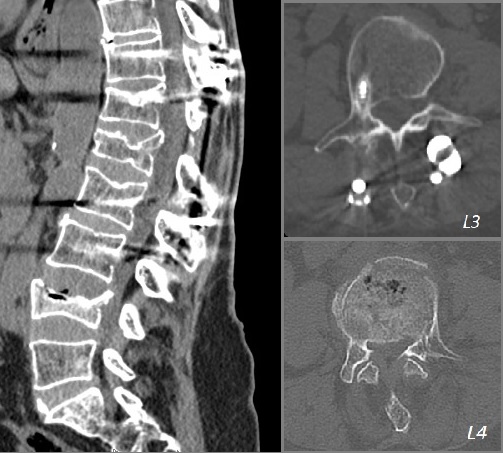

Yapılmış olan MRG incelemesinde L4 vertebrasında yeni kırık görülüyordu. Yaptırılan direkt grafi ve BT incelemelerinde ise daha önce yapılmış olan T11-L3 stabilizasyon sisteminin alt uçta gevşeyerek disfonksiyone olduğu saptandı.

L4 vertebrasında akut kırık ve kanal daralması MRG görüntüsü

Resim 1: MRG incelemelerinde L4 vertebrasında akut/subakut dönemde patlama kırığı ve bu seviyede belirgin kanal daralması izlenmekte.

Bilgisayarlı tomografi kesitleri - Vida gevşemesi ve faset ayrışması

Resim 3: Bilgisayarlı tomografide L3 seviyesinde sağda vida gevşemesi (vida etrafında sklerotik halo), L4 vertebrasında ön ve orta kolonda yükselik kaybı, korpusa ve sol pediküle uzanan kırık hatları ve ayrıca bu seviyede solda belirgin olarak faset eklemlerde ayrışma görülmekte. Sisteme ait diğer vidalar gevşememiştir. L2-3 seviyesinde kısmi, yukarıdaki seviyelerde tam faset füzyonu vardır.